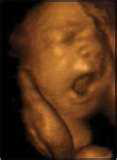

corpul copilului este în întregime format. La

acţiunea unui stimul palmar, el încearcă să se prindă. În caz de

zdruncinături, ca să evite lovirea, el poate întoarce capul. Degetele au

deja delicate,

fragede unghii. Îşi poate mişca mâinile şi picioruşele. La

atingerea obrajilor şi a buzelor, copilul dă să surâdă.